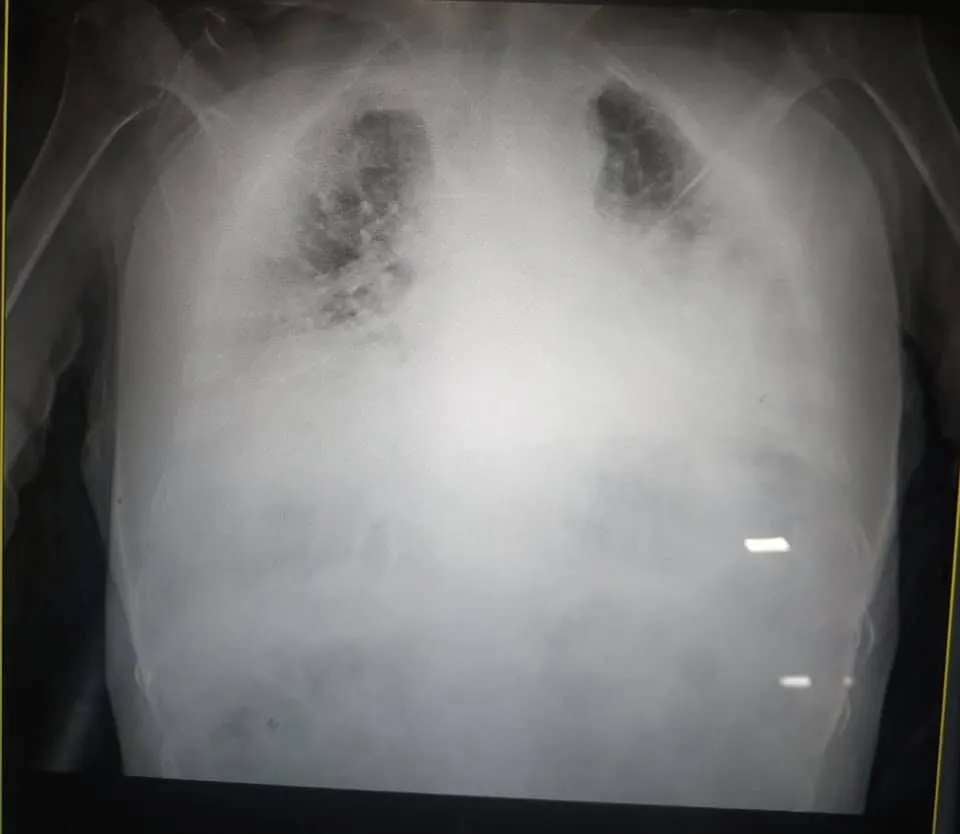

Легені хворого повністю пошкоджені хворобою. Про це зазначила Ірина Заславець на своїй фейсбук-сторінці.

Це одні з найстрашніших легенів, які я бачила в житті, – сказала мені щойно очільниця реанімації клінічної лікарні швидкої медичної допомоги Львова,

– написала жінка.

Легені хворого на коронавірус / Фото Facebook Ірина Заславець

Вона додала, що з Винників до медзакладу привезли 18 пацієнтів з коронавірусом. 7 із них – в реанімації. Усі в критичному стані.